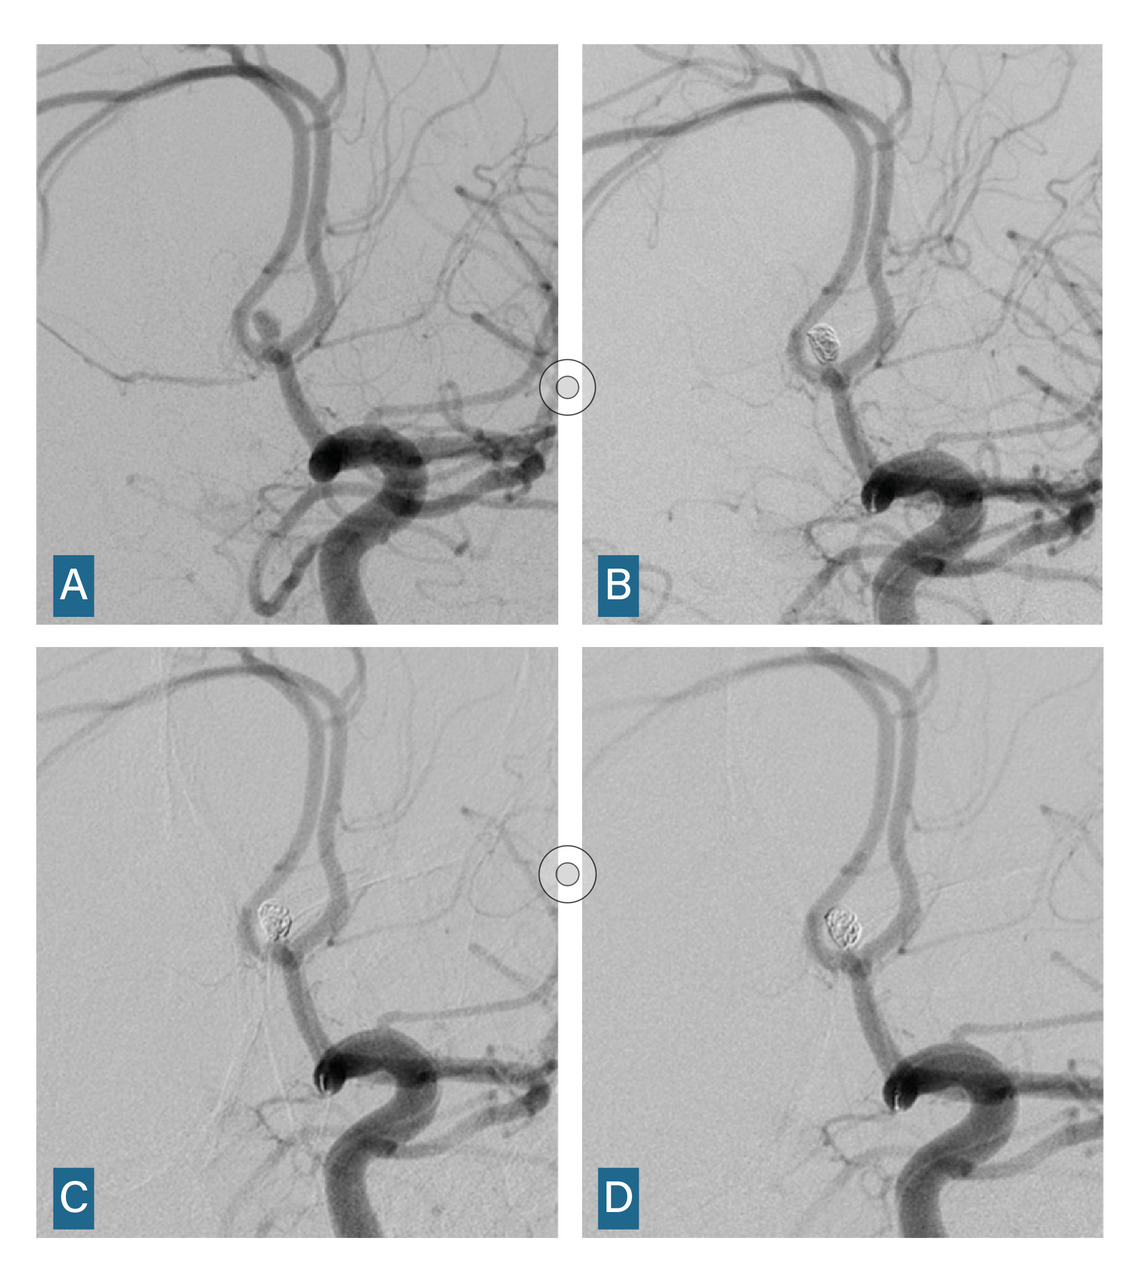

L’imagerie cérébrale intervient également dans le suivi et la prise en charge des complications tardives. En cas de vasospasme résistant au traitement ­médical optimal, une procédure endo­vasculaire est menée, incluant une dilatation chimique et éventuellement mécanique (fig. 5).